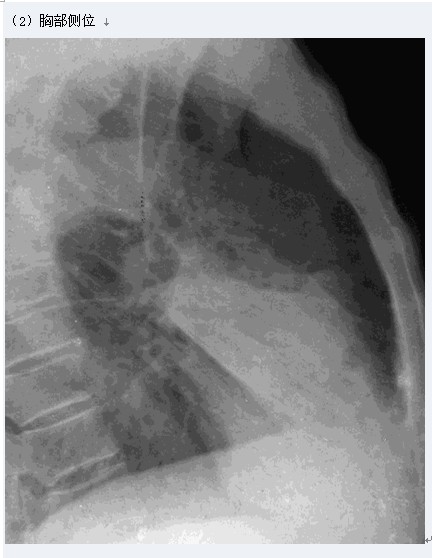

大葉性肺炎

圖示為右肺中葉大葉性肺炎

(1)胸部正位